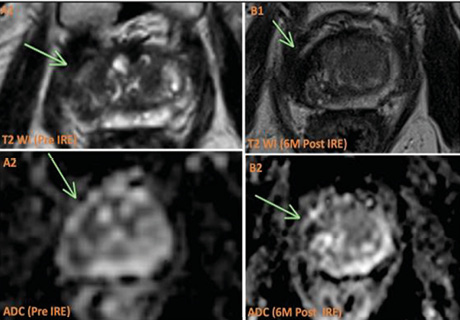

Візуалізаційний контроль проводився в стандартні терміни за допомогою КТ / МРТ із внутрішньовенним підсиленням (рис. 5).

Рис. 5. На передопераційному КТ-зображенні виявлено пухлину в середньому сегменті правої нирки (а). Електроди були введені ззаду, а для точного позиціонування голок електродів використано зображення 3D-реконструкції (b–d). Повторні КТ-зображення одразу після НОЕ та через 1, 3, 12 міс не виявили жодного підсилення в ділянці абляції (e–h) [цит. за 5]

У одного пацієнта відмічалося підшкірне метастазування в голковий тракт, яке було видалено хірургічним шляхом під місцевим знеболенням (рис. 6). Ще в одного хворого через 6 міс після НОЕ виявлено часткове підсилення початкової зони абляції, що було розцінено як рецидив, з приводу чого виконано повторну НОЕ. Після цього не зафіксовано жодних ознак рецидиву на наступних візуалізаційних дослідженнях у жодного з пацієнтів.

Рис. 6. Метастаз голкового тракту виявлено через 3 міс після НОЕ (а). Підшкірну резекцію виконано під місцевою анестезією (b). Повторне МРТ-підсилення через 6 міс після резекції свідчить про повне видалення метастазу без рецидиву (с) [цит. за 5]